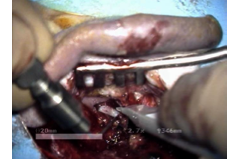

Telemani- puliertes Operieren

Benötigt der Arzt für einen schwierigen Operationsschritt ein präzises Instrument, so kann der Manipulator über den Gelenkarm schnell in das OP-Gebiet eingeschwenkt werden. Die Standardinstrumente werden einfach in die sterilen Instrumentenaufnahmen eingeklipst. Die Instrumente können dann über eine Joystick-Steuereinheit vom OP-Tisch aus bedient werden. Die Bewegungen des Chirurgen werden dabei skaliert, sodass eine große Bewegung der Joysticks zu einer kleinen Bewegung des Instrumentes führt. Der Arzt kann jederzeit auch per Hand weiteroperieren.